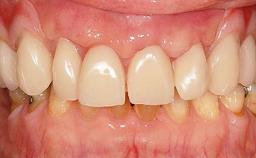

A 31-year-old man presented to our clinic 30 days after a motor vehicle accident in which he had suffered a dentoalveolar fracture in the anterior maxilla, including avulsion of teeth 12 and 11 and luxation of tooth 21. He was first treated on the night of the accident in a small city hospital with no oral and maxillofacial surgeon on the staff. A wired retention had been applied and the teeth repositioned to the best of the clinicians’ abilities. When he first presented to our care, the patient showed extrusion of teeth 12 and 11 associated with gingival recession due to bone loss in the anterior maxilla, and the stainless steel wires were still present.